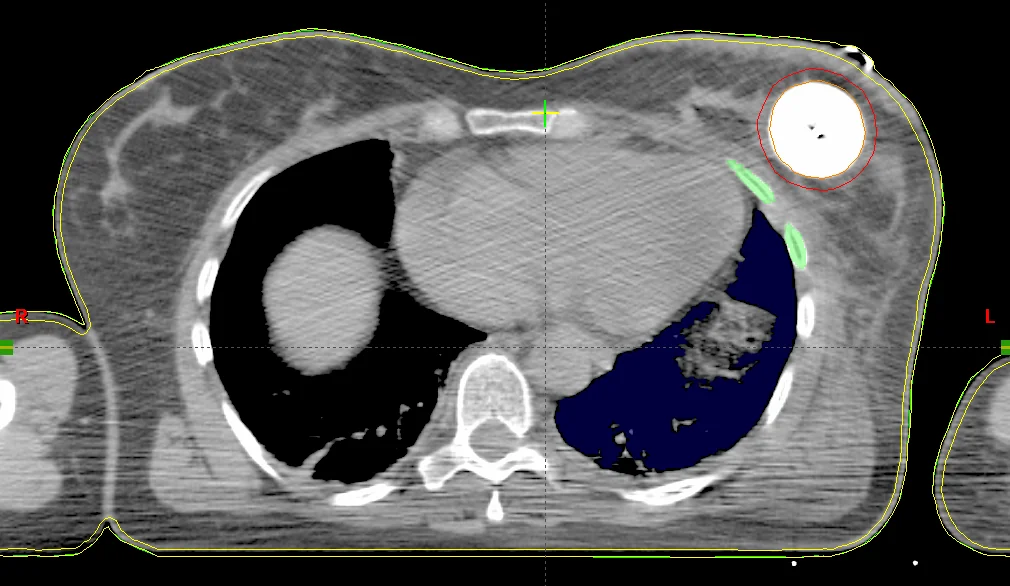

Der MammoSite-Applikator ist ein füllbarer sphärischer Silikonballon, der intraoperativ in der Kavität des entfernten Tumors platziert wird. Der wird Ballon wird mit einem Gemisch aus isotoner Kochsalzlösung 0,9 % und Kontrastmittel (z. B. in einem Verhältnis von 10:1) gefüllt. Das iodhaltige Kontrastmittel hebt den Ballon auf den CT-Bildern vom Brustgewebe ab, sodass er für die Bestrahlungsplanung gut konturiert werden kann. Eine zu hohe Kontrastmittelkonzentration (Empfehlung: <10 %) kann bei Berechnungen mithilfe des TG-43-Algorithmus, der zur Berechnung eine reine Wasserumgebung annimmt, zu großen Dosisabweichungen führen. Das liegt vor allem an dem hohen Iodgehalt in den Kontrastmittellösungen, das aufgrund seiner hohen Dichte zu Dosisreduzierungen führen kann, die vom TG-43-Algorithmus nicht berücksichtigt werden. In mehreren Sitzungen wird die Quelle durch einen Zweikanal-Katheter in den Ballon gefahren. Der Durchmesser des Ballons variiert je nach Patient und Ausführung des Ballons. Um den hohen Ansprüchen komplexer Dosisverteilungen gerecht zu werden, gibt es seit einiger Zeit Multilumen-Varianten (nicht sehr verbreitet in Deutschland), die unter Verwendung mehrerer Katheter weitere Haltepositionen ermöglichen.

Nach der chirurgischen Entfernung des Tumors, wird der MammoSite-Applikator eingesetzt und verweilt dort für die gesamte Behandlungszeit (ca. eine Woche). Am zweiten Tag wird ein Planungs-CT gefahren und basierend auf der Anweisung ein Bestrahlungsplan erstellt. In den letzten drei Tagen wird in je zwei Sitzungen pro Tag eine Dosis in einem bestimmten Abstand, in der Regel in 0,5 cm Gewebstiefe bzw. 0,5 cm von der Ballonoberfläche appliziert. Die Haut- und Rippendosis sollten eine Maximaldosis (z. B. 1,5 Gy pro Fraktion) nicht überschreiten, und bilden somit die limitierenden Faktoren der Behandlung. Je nach klinischer Erfahrung, variieren die Dosierungskonzepte und tolerierbaren Maximaldosen in den Risikoorganen.

Sofern in der Computertomographie um den Ballon große Lufteinschlüsse zu sehen sind (z. B. weil die Kavität das maximale Ballonvolumen überschreitet, oder dieser nicht vollständig aufgefüllt wurde) müssen diese ebenfalls berücksichtigt werden, da Dichteinhomogenitäten vom am weitesten verbreiteten TG-43-Algorithmus nicht berücksichtigt werden. Zu diesem bekannten Problem existiert bereits eine Reihe von Publikationen. Diese beschäftigen sich überwiegend mit den Auswirkungen vom Kontrastmittel, von Lufteinschlüssen am und im Ballon und mit dem Umgebungsmedium, dass im TG-43-Formalismus als Wasser angenommen wird, woraus eine erhöhte Rückstreuung resultiert.